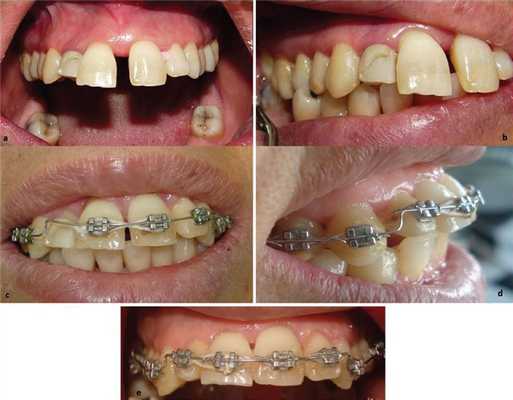

После стабилизации пародонтологического статуса и сокращения пародонтальных карманов до 15% или менее, после установки прочных связей для регулярных визитов проведено фиксирование несъемной ортодонтической техники на всю зубную дугу, проволочная техника интрузии и выравнивания центральных резцов. Нагрузка прилагалась равномерно на каждый зуб 10-15 г (проверено при помощи Correx, HAAG-STREIT Holding, AG) согласно индивидуальному пародонтальному статусу. Для предотвращения якорной убыли мы прибегли к методике полной дуги, корректируя приспособления каждые 4 недели. Инструкции по гигиене полости рта, а также сглаживание поверхностей корней проводилось каждые три месяца. В целом ортодонтическое лечение длилось от 10 месяцев до 2 лет в зависимости от пациента (Фото 1). Затем терапия переведена в фазу ретенции. В конце лечения несъемная аппаратура расфиксирована и зафиксированы ретейнеры (Braided нержавеющая сталь, 0/38 мм, Dentaflex, Germany) на нижнюю и верхнюю челюсть. Снова даны рекомендации по гигиене полости рта.

Фото 1: (а,b) Фронтальный и боковой вид смещенного правого верхнего центрального резца, связанного с утратой кости у пациента с агрессивным локализованным пародонтитом (патологическое перемещение) после лечения тканей пародонта и перед наложение ортодонтической силы (с,d) 6 месяцев ортодонтического лечения техникой полной дуги для интрузии переднего смещенного зуба, (е) конец ортодонтичечского лечения